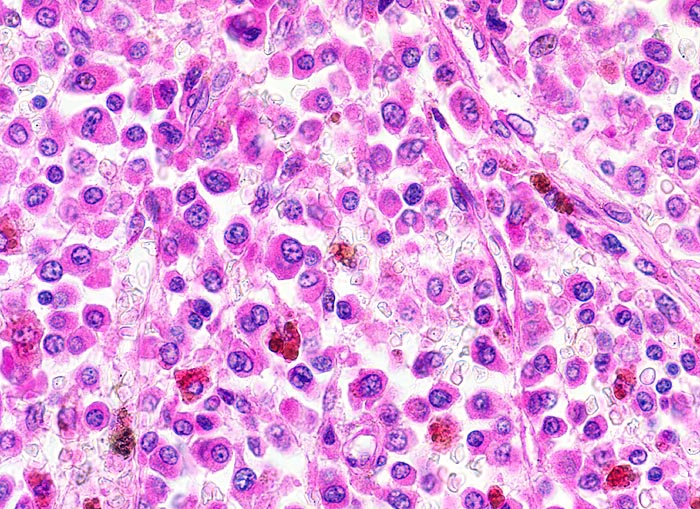

Morphologische Merkmale:

• Knochenmarkstanze mit nodulärer Hyperzellularität des blutbildenden Marks.

• In den hyperzellulären Arealen dichte Rasen neoplastischer atypischer Plasmazellen.

• In dieser Giemsa-Färbung sind die Plasmazellen gut erkennbar. Die Plasmazellen sind polymorph, vereinzelt mehrkernig. Exzentrisch im Zytoplasma lokalisierte vergrösserte Radspeichenkerne . Reichlich violettes Zytoplasma mit paranukleärer Aufhellung. Zellkerne teils mit vergrössertem Nukleolus.

• Ausserhalb der Plasmazellrasen findet sich spärlich residuelles blutbildendes Knochenmark.